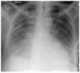

Cardiomegaly

Cardiomegaly (sometimes megacardia or megalocardia) is a medical condition in which the heart is enlarged. As such, it is more commonly referred to simply as "having an enlarged heart". [Source: Wikipedia ]